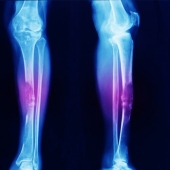

Apa saja alasan untuk amputasi dan mengharuskan Anda menggunakan kaki palsu murah dari GO JOP? Amputasi adalah operasi pengangkatan bagian tubuh, biasanya lengan atau kaki. Ada tiga alasan utama untuk amputasi.

- Anggota tubuh telah terkena gangren, yaitu ketika jaringan tubuh mulai mati akibat kekurangan suplai darah.

- Ada bahaya yang mengancam jiwa bagi kesehatan seseorang, seperti ketika bagian tubuh terkena kanker atau infeksi serius.

- Anggota tubuh mengalami trauma serius, seperti cedera yang menghancurkan anggota tubuh atau luka yang signifikan.